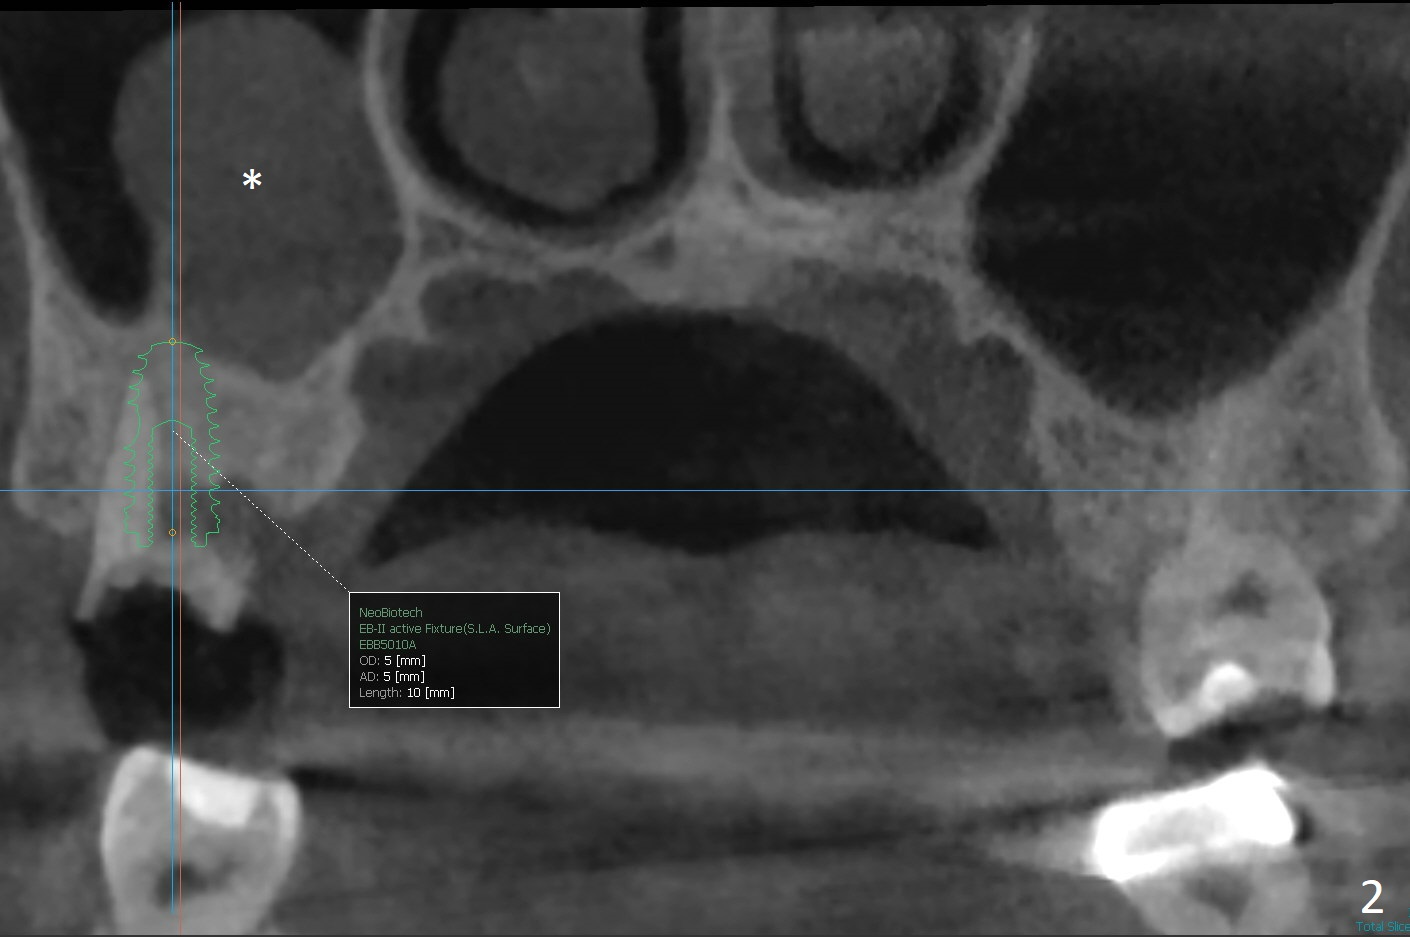

A 51-year-old man agrees to have #2 residual root to be extracted for implant. Panoramic X-ray (Fig.1) and CT coronal section (Fig.2) show maxillary sinus mucocele (*). A 5x10 mm implant will be placed not to intrude into the sinus (Fig.2,3). In case sinus membrane perforation, prepare PRF membranes for repair. The apex of the implant will be engaged to an apparent sinus septum for stability (Fig.4,5,7 arrowheads). Fig.4,5,6 are sagittal and coronal sections and 3-D image of Fig.3 without an implant at #2, while Fig.7 is the inferior view of Fig.6 (arrow).